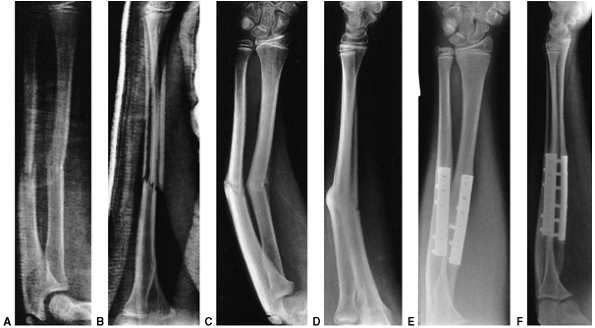

an oblique growth arrest line (41) (Fig. 33.3). Magnetic resonance imaging (MRI) may also be useful to detect early physeal arrest (42,43).

![]() |

Figure 33.3 Distal tibial growth arrest. A: Distal tibial physeal Salter-Harris type IV injury treated with cast immobilization without reduction. B:

Two years later, there is varus angulation to the distal tibia from a medial physeal bar. The Harris growth arrest line is not parallel to the distal physis, and does not extend across the entire width of the metaphysis. |

Figure 33.4 Growth arrest patterns. A: Type I is peripheral growth arrest with a peripheral bony bar. B: Type II is central growth arrest with central physeal tethering. The peripheral physis and perichondrial ring are intact. C:

Type III is combined growth arrest, demonstrating a linear bar involving the peripheral and central portions of the physeal plate. This type of growth arrest is more typical after a Salter-Harris type III or IV fracture. |